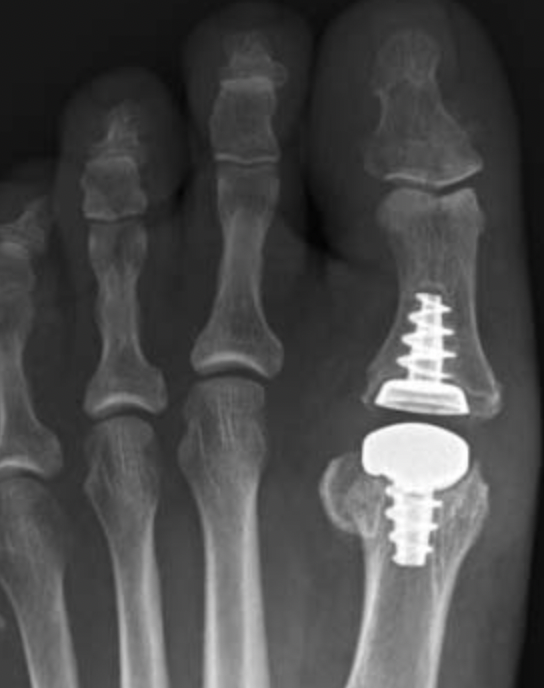

Operative Options

Osteotomy / Arthrodesis / Arthroplasty / Keller's procedure (excision arthroplasty)

He et al J Foot Ankle Surg 2021

- systematic review of 1st MTPJ arthrodesis v arthroplasty in RA

- no difference in pain score, outcome, or reoperation rates